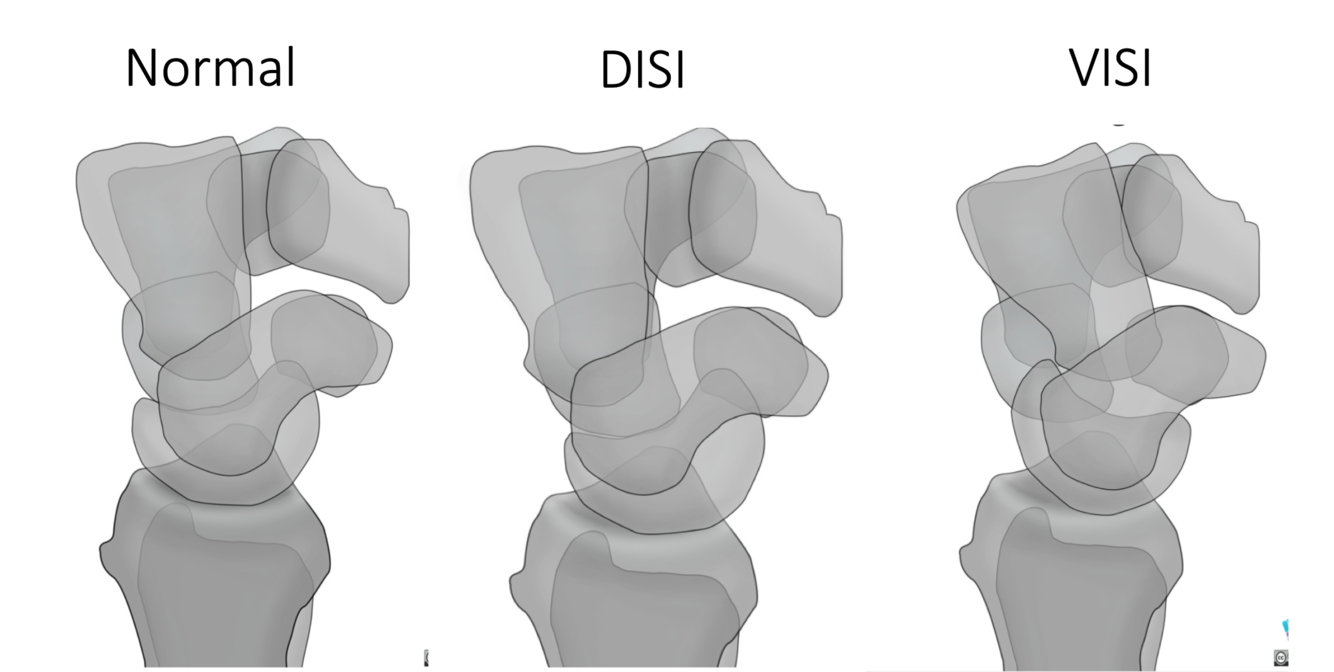

Name each alignment show in the picture

Scapholunate angle in DISI

Scapholunate angle > 60 deg

Normal scapholunate angle

30-60 deg

Scapholunate angle in VISI:

<30 deg